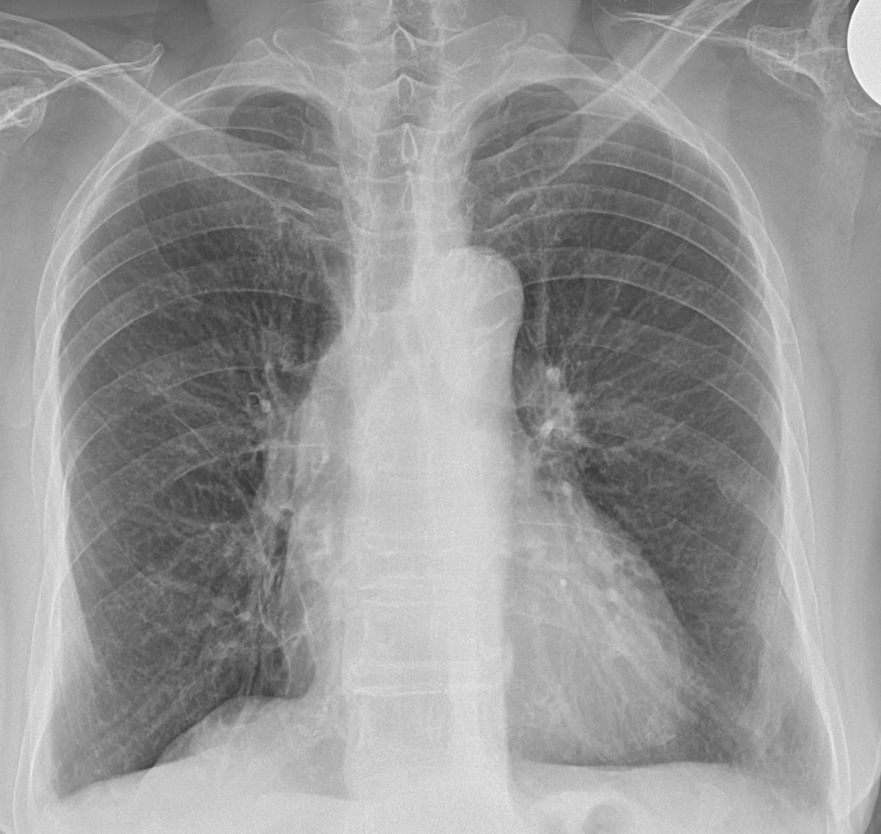

1) 흉부 X선 검사

흉부 X선(엑스레이) 검사는 흉막비후를 발견하는 가장 기본적인 검사입니다. X선 사진은 폐와 가슴 부위의 기본적인 구조를 보여주기 때문에, 흉막이 두꺼워진 부분이 있다면 이 검사로 확인할 수 있습니다. X선 사진에서 흉막비후는 폐의 가장자리나 가로막과 가까운 부위에서 선명한 두꺼운 그림자로 보입니다. 특히 흉막비후가 폐 아래쪽에 있을 때, 늑횡격막각이 흐려지거나 소실된 모습으로 나타납니다.